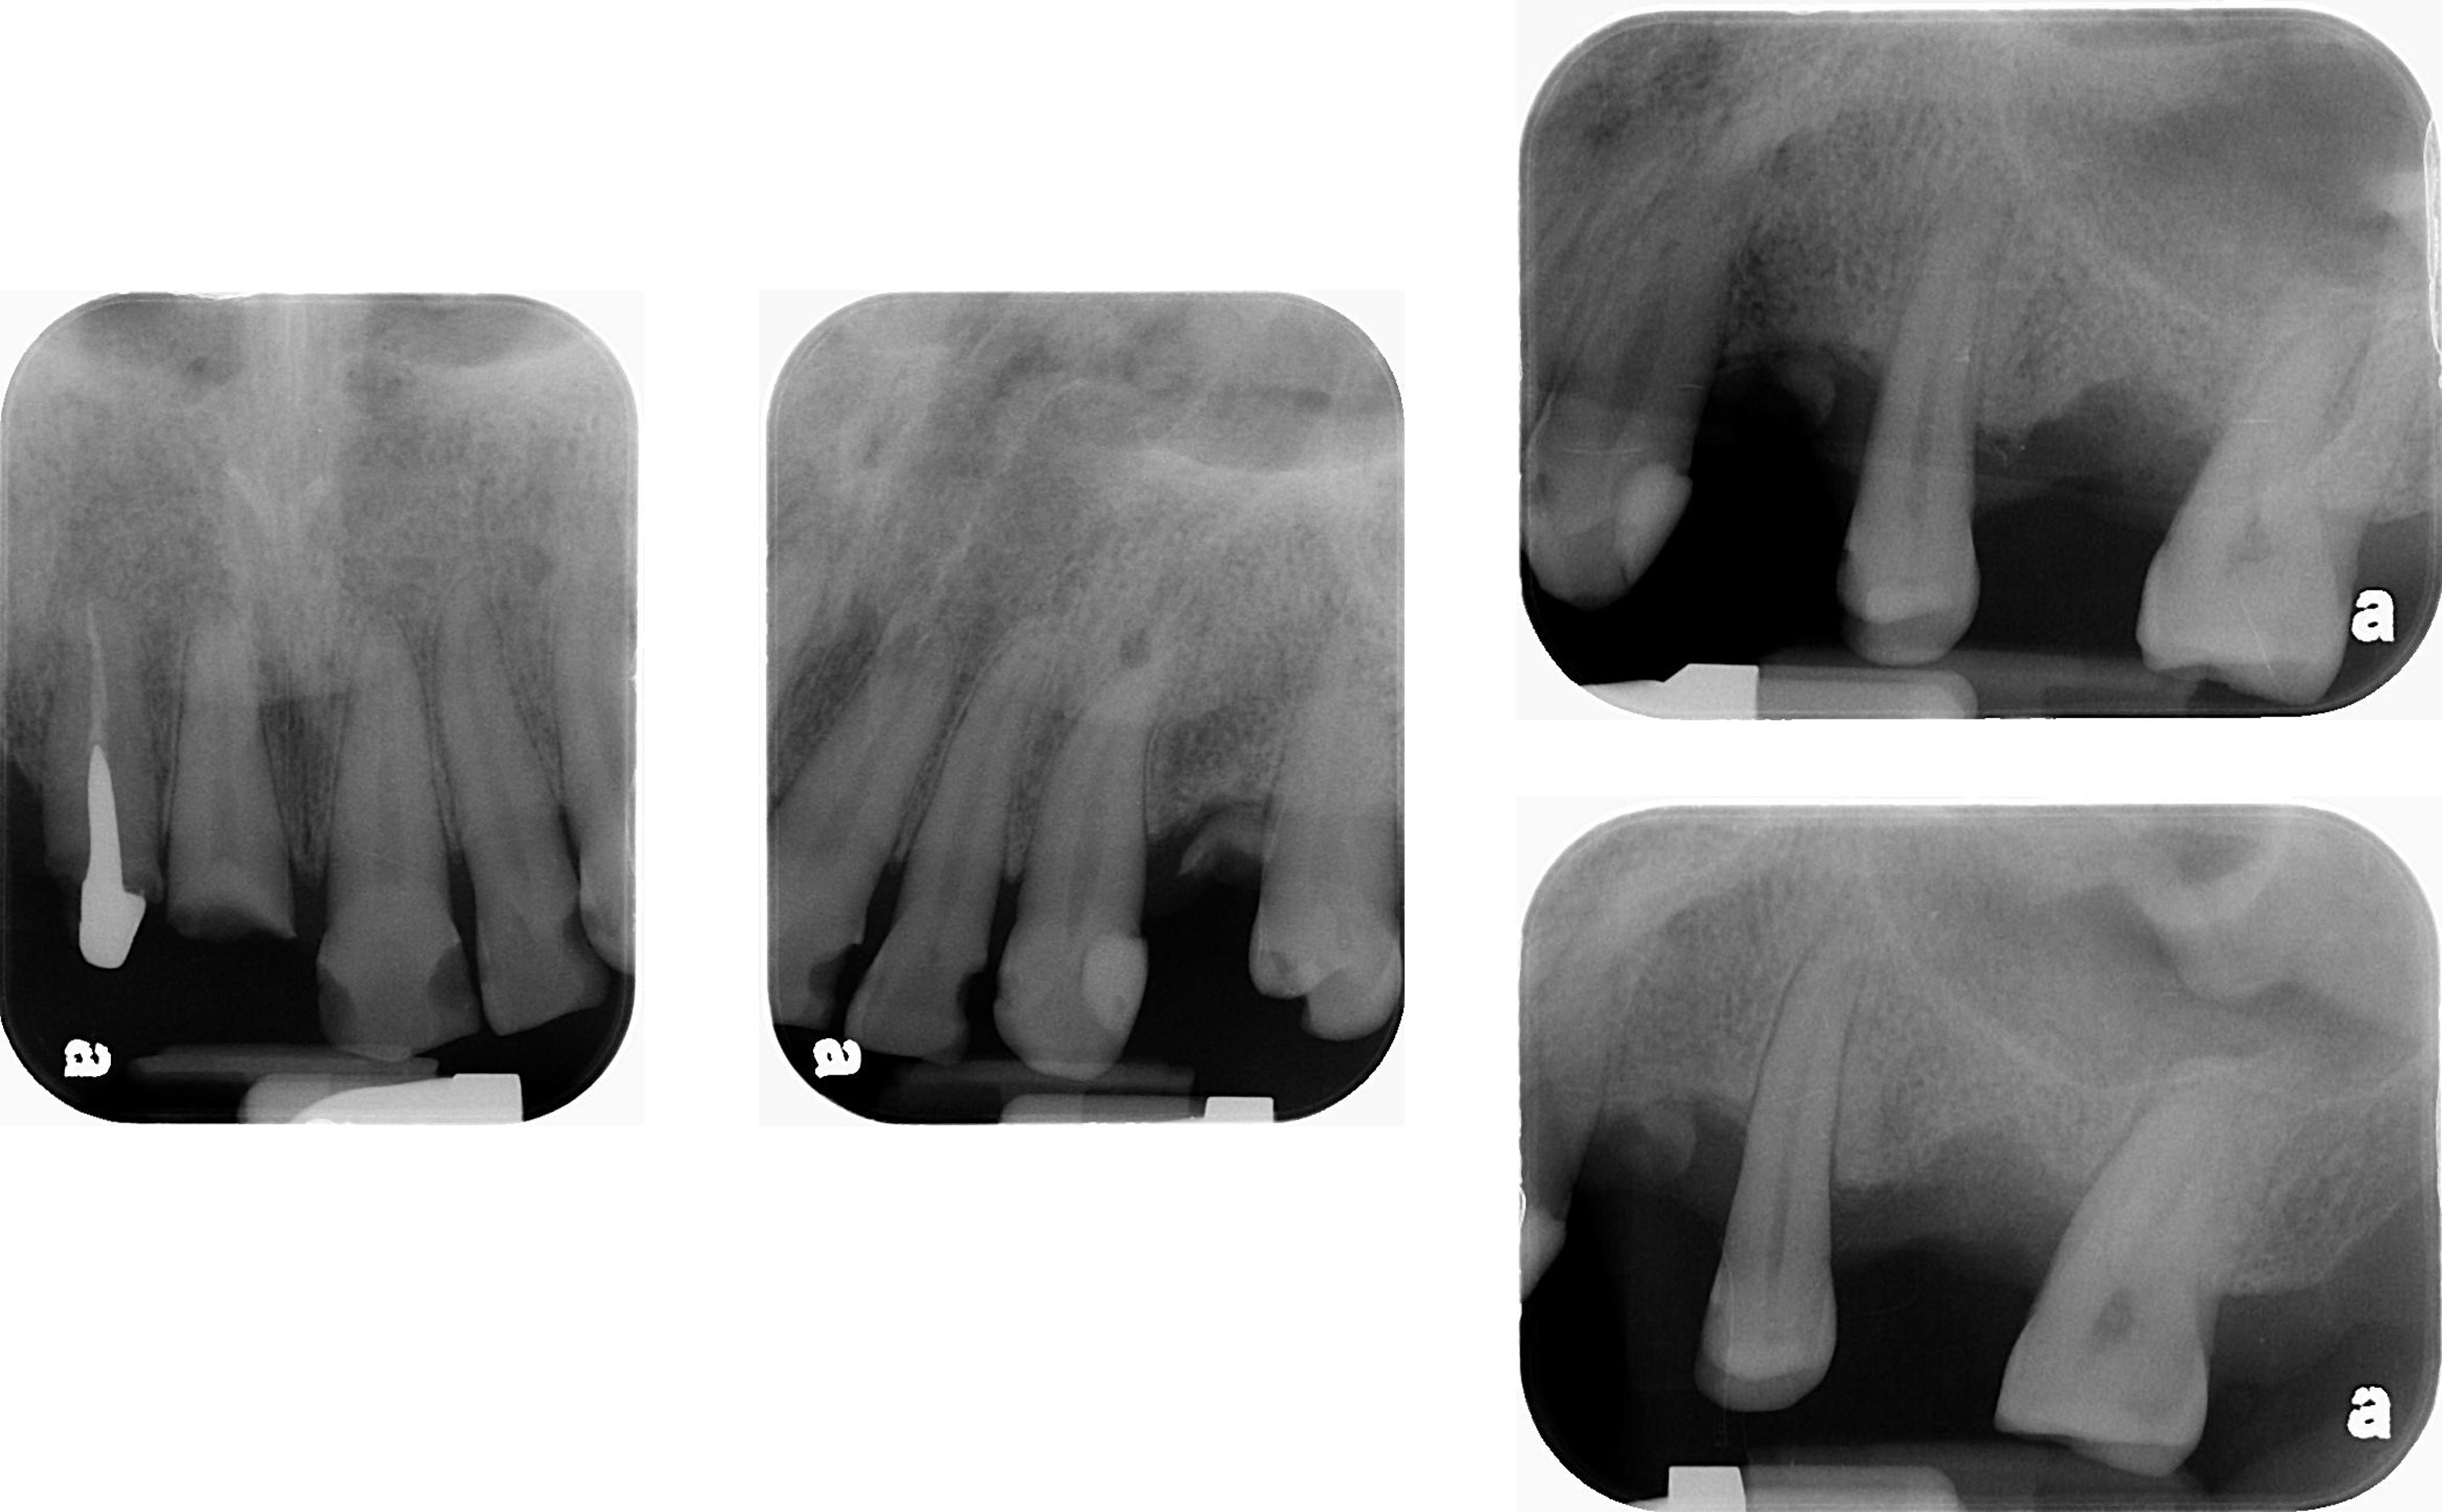

治療前上下顎因口外手術,造成咬合喪失

治療前,咬合喪失,磨耗

治療前,殘根與牙周支撐不良

術後X光片

術前、術後比較